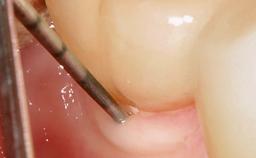

A 70-year-old female patient was referred by her general dentist to the periodontist for assessment and management of an infection associated with implant 36. The general dentist had noted suppuration on probing during examination.